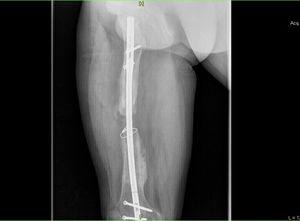

Femur

The fracture of the femur in the traffic accident , 6 operations, an infection, an external fixator, and now intermediate wedge..

Need bone graft